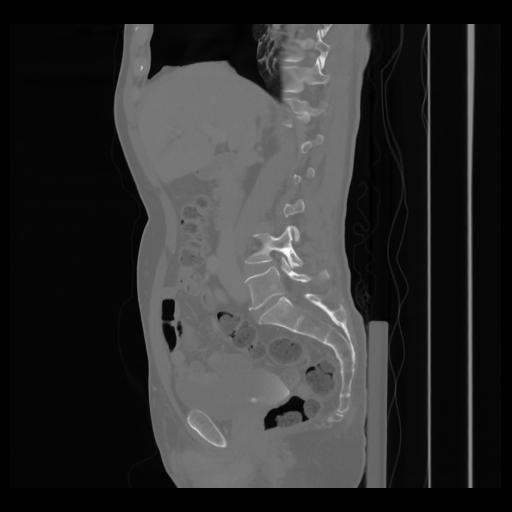

36 CUERPO,CE,Sagittal,3.000,CUERPO,Sagittal,